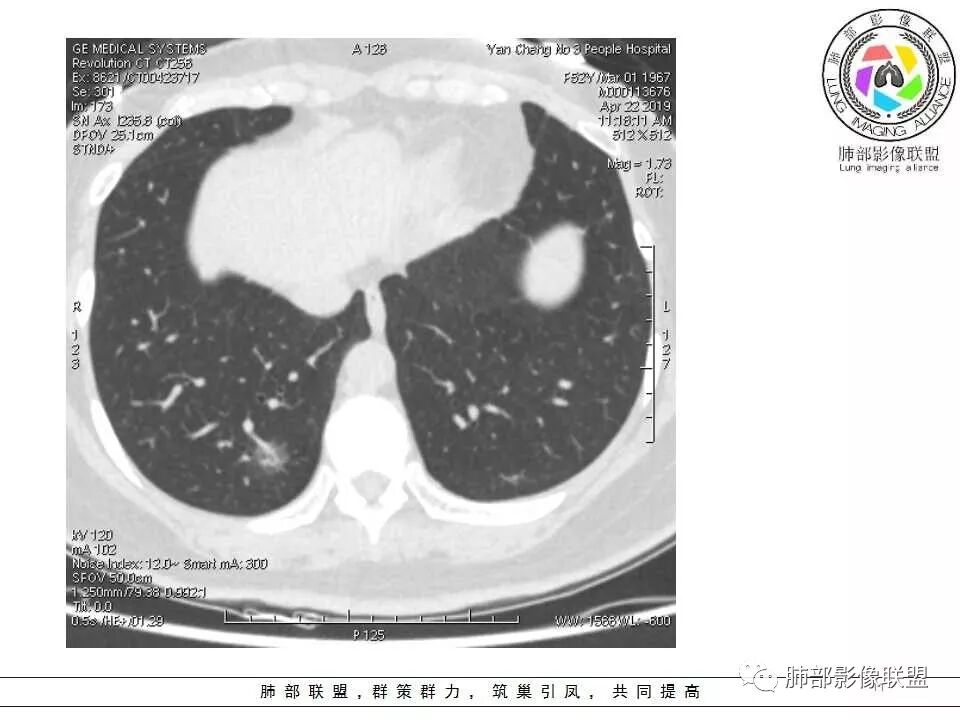

大家考虑恶性的依据?炎性的依据?首先这是不是磨玻璃结节?依据是啥?

因为密度比肺组织高,但是又遮盖不了血管,所以GGO明确

是pGGO?mGGO?

实性的部分超过10%——mGGO

GGO边缘清不清?依据?

部分清,部分不清

依据:能不能沿GGO边缘画出一个边界

能否勾勒出边界?是否有血管?

排除血管的边缘,边界清吗?

可惜的是背景也模糊了一些

患者后来到上海做了手术,电话回访告知结果为粘液腺癌